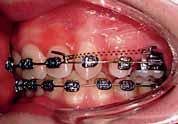

The oral hygiene of the patient and the carious lesions were addressed prior to the start of the fixed appliances treatment. The patient’s compliance was good and treatment progressed without encountering major problems. The reduction of the overbite was achieved initially with the anterior bite plane then a reverse curve of Spee was placed in the lower archwire to control the overbite. A Trans-Palatal Arch (TPA) with Nance button was fitted prior to the extraction of the upper premolars in order to reinforce the anchorage (Figure 6). The treatment continued with the use of Class II traction on both sides and space closure mechanics.

The next phase of treatment involved the fitting of the Trans-Palatal Arch (TPA) and the removal of the upper first premolars. Because of the increased overjet, this was a case of maximum anchorage and any mesial movement of the upper buccal segments was not desirable (Figure 6). It remains equivocal in the literature whether TPA appliances can provide anteroposterior anchorage. In fact, recent evidence suggested the contradictory 8 Alternatively the anchorage issue in this case could have been addressed with a Temporary Anchorage Device. The increase